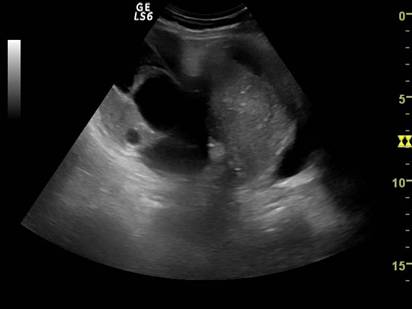

Tumorile ovariene

Ecografia abdominala si transvaginala trebuie sa raspunda suspiciunilor legate de malignitate sau benignitate. In functie de tipul de ecogenitate interna, tumorile ovariene se pot clasifica in [2,5,6] :

tumori ovariene pur chistice

tumori ovariene pur solide

tumori mixte ovariene

Criteriile de evaluare sonografica a acestora sunt:

Tumori ovariene chistice